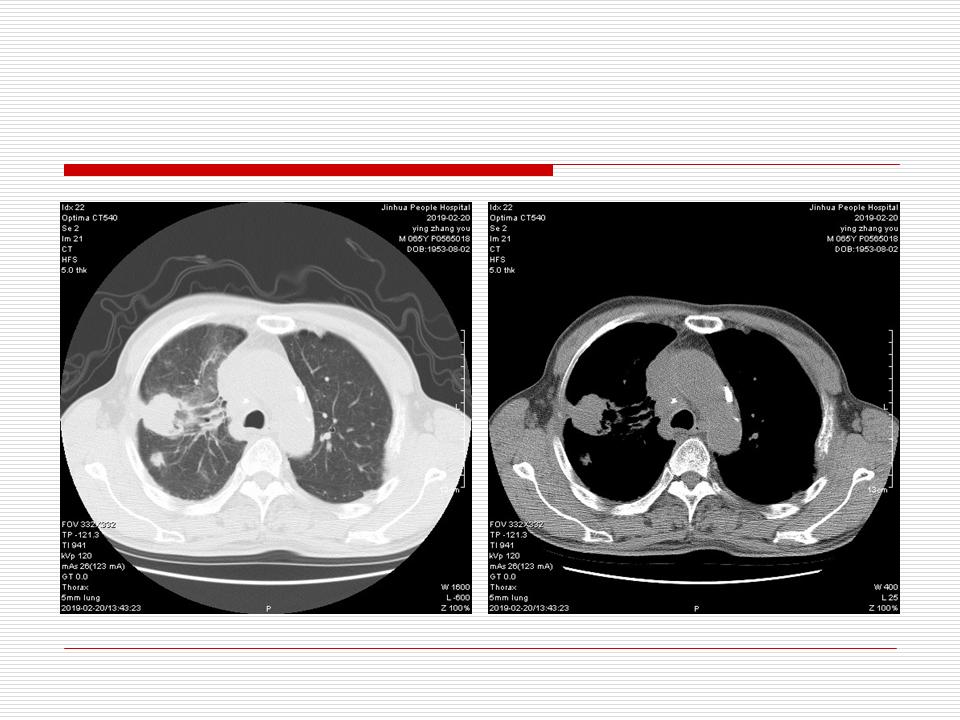

肺部阴影永恒且最重需要鉴别的是:到底是炎症还是肿瘤?但临床的病例中的影像表现难以界定或有些肿瘤特征,同时又有些炎症特点是非常常见的情况。作为临床医生我们怎么去总结分析,并找到之所以是炎症或之所以是肿瘤的细微差别或特点非常重要,也非常有用。2019.12.7浙江省2019年胸心外科学学术年会在宁波召开时,我的临床病例分析与经验总结<那些像肺癌的炎症与像炎症的肺癌>获得在大会交流的机会,以下为该PPT的内容,与你分享,希望对同道有益,有借鉴与启迪。若有探讨与进一不完善的建议,欢迎文末留言讨论: